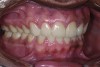

Figure 20. Postoperative 1:2 retracted frontal view.

Figure 20

The final restorations depicted restoration of form, function, and beauty, with good harmony of restoration and the periodontium (Figure 19 through Figure 25). MIP was in harmony with CR, and right and left lateral excursion discluded all posteriors with anterior group function. The postoperative orthopantomogram (OPG) (Figure 26) shows the treatment done while maintaining the vitality of anterior teeth.